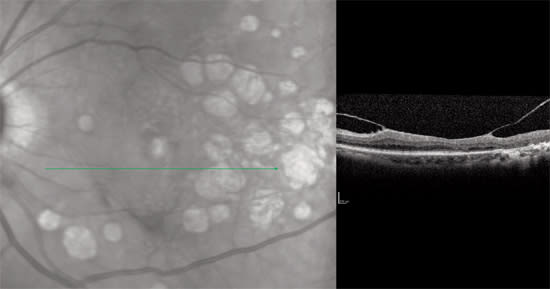

The scans shown here illustrate the utility of spectral domain OCT for imaging a range of pathology (Figures 1–3).

Figure 3. Ocular histoplasmosis and choroidal neovascularization is seen in a 55-year-old woman with a history of POHS in the fellow eye, now with blurred vision and distortions. OCT demonstrates a deep area of histo spots and adjacent subretinal fluid.